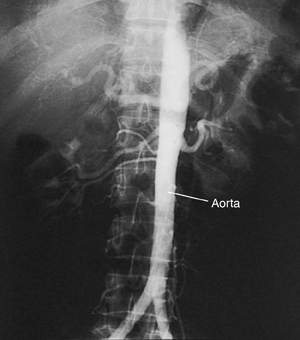

Aortic Angiogram

An aortic angiogram is a test that takes pictures of the aorta. This is the main blood vessel that carries blood from your heart to the rest of your body. The test can show problems with your aorta. These include a blockage or an aneurysm (a balloon-like bulge in the wall of the aorta).

The catheter is slowly advanced through the blood vessel and into the aorta. Live X-rays (fluoroscopy) are used to help guide this process. The X-rays are viewed on a video screen.

Once the catheter is in the right place, contrast fluid (dye) is sent through the catheter. X-ray pictures are then taken of the aorta. The contrast fluid (dye) makes the aorta easier to see on the pictures.